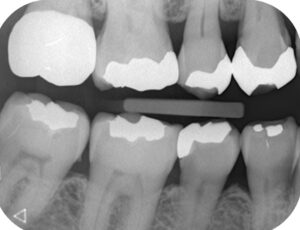

見た目ではわからない「歯と歯の間のむし歯」も、X線なら早期に発見できます。

成人では6~24か月ごとの撮影が推奨されています(Pitts, 1996)。